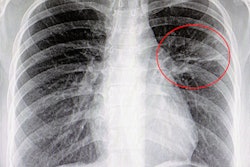

The SpectralDR technology enables dual-energy subtraction, providing bone and tissue differentiation with a single standard x-ray exposure. It acquires three images simultaneously (digital radiography, bone, and soft tissue dual-energy x-ray images). The technology mimics the workflow, dose, and techniques of mobile digital x-ray detectors.